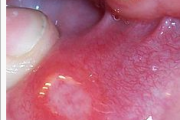

Tekitajad ja kliiniline pilt Gingivostomatiit – Tekitaja herpessimplex-viirus – Primaarinfektsioon, mille üldnähtudeks on palavik, halb enesetunne ja peavalu. – Herpeseville leidub põskede limaskestal, huultel ja keelel, sageli lõhkevad need kiiresti ja jätavad väikese erosiooni. – Loe edasi »